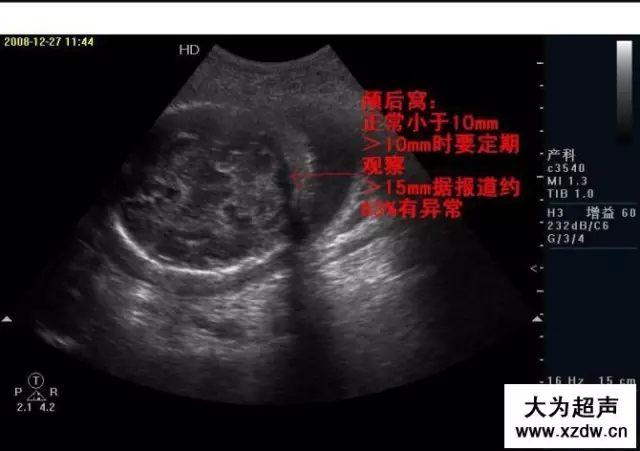

產科超聲正常圖片